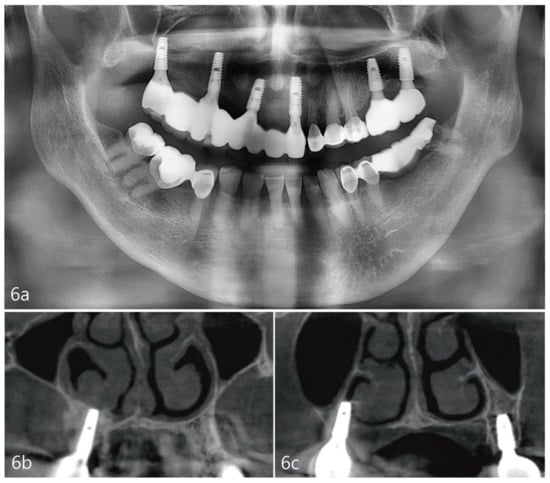

The case report presented here demonstrates no clear perforations with uneventful healing for the patient. Immediately following the surgery, CBCT analysis of the implant placement and bone augmentation demonstrated adequate elevation and grafting in the lateral nasal wall of the inferior meatus (Figure 3a,b). Figure 3a specifically demonstrates a well-defined periphery of the grafted site along the implant placed at site #4. The implant at site #2 was placed utilizing the transcrestal approach and depicts partial bony engagement of the lateral wall (Figure 3b). The surgical site healed uneventfully and no early or late complications were documented. Six months post-surgery, radiographic and clinical examination revealed stable implants engaged with the augmented bone during the uncovering. The bone biopsy harvested at implant uncovering and the placement of healing abutments were evaluated morphometrically. The core-stained slides were examined and depicted in entirety in Figure 5a, at 1× resolution. Figure 5b at 10× resolution, provides a detailed view of the newly formed bone and residual calcium phosphate particles. The newly depicted bone demonstrates osteocytes encased within and associated active osteoclast and osteoblasts cells. The actively remodeled sites are flanked by osteoid deposits and residue calcium phosphate particles. Histologically, the site does not demonstrate any necrotic bone, bacterial debris, or invasion. The site demonstrates active bone remodeling, indicating vital bone undergoing bone turnover where the biphasic calcium phosphate is eventually resorbed and replaced by new bone. Furthermore, clinical and radiographical observations reveal no associated complications such as marginal bone loss around the implants placed at sites #2 or #4 or soft tissue ingress, etc. (Figure 6a–c). The patient’s airways continue to remain patent, with no clinical complication or masticatory problems reported in subsequent follow-ups.

Figure 6. (a). Panoramic radiograph 2 years after prosthesis delivery. (b). Coronal view of the CBCT at the #4 site showing no marginal bone loss around the implant or other abnormal findings. (c). Coronal view of the CBCT at the #2 site showing no marginal bone loss around the implant or other abnormal findings.